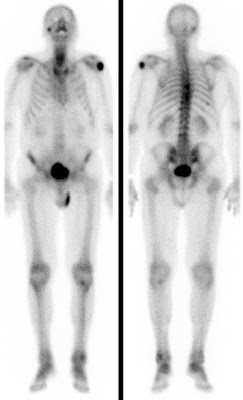

Bei der Skelettszintigraphie werden schwach radioaktiv markierte Phosphatkomplexe verabreicht, die zunächst im Blut durch den Körper zirkulieren und im Verlauf von 2-3 Stunden ausreichend in den Knochen eingebaut werden, so dass dann der Knochenstoffwechsel abgebildet werden kann.

Es bestehen die Möglichkeiten, gleich nach Verabreichung der Phosphatkomplexe die Durchblutung zu untersuchen und auf den Spätaufnahmen den Knochenumbau zu beurteilen. Bei der Skelettszintigraphie gibt es keine Unverträglichkeitsreaktionen auf die verabreichten Radiopharmaka. Im Gegensatz zu vielen Röntgenkontrastmitteln sind die verwendeten Radiopharmaka auch nicht nierenschädlich.

Die Hauptfragestellungen bei der Skelettszintigraphie betreffen die Feststellung evtl. Knochenmetastasen bei Krebserkrankungen und die Unterscheidung von primär entzündlichen vs. primär degenerativen Gelenkerkrankungen, also rheumatischen Grunderkrankungen mit Skelettbeteiligung vs. (aktivierten) Arthrosen.

Darüber hinaus ist die Skelettszintigraphie häufig auch bei der Abklärung unklarer Knochenschmerzen sehr hilfreich, etwa zur Feststellung evtl. Knochentumoren, von Prothesenlockerungen, einer Osteomyelitis, von Frakturen, von Knocheninfarkten etc.